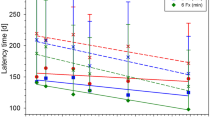

MRI measurements after carbon ion and photon irradiation revealed the same morphological alterations in the MR images ranging from the development of edema, syrinx (dilatation of the canalis centralis) and contrast agent accumulation up to the final development of the radiation-induced myelopathy (Fig. 3). The latency time until development of paresis grade II, however, was significantly shorter for carbon ions (136 ± 10 d) than for photons (211 ± 20 d). Evaluation of the DCE-measurements exhibited a continuous increase of the parameters ve and Ktrans with increasing damage of the BSCB, however, no significant differences between carbon ion and photon irradiation was found, except for the shorter latency time. No significant changes were found for the parameter vp.

No protective effect of ramipril™ for the development of radiation-induced myelopathy after carbon ion or photon irradiations was observed. However, a modality and dose dependent prolongation of latency time of 23 ± 8 d after carbon ion irradiation and 16 ± 3 d after photon irradiation was found.

The MRI-based longitudinal study enables a non-invasive investigation of occurring radiation-induced effects during the symptom free latency time. We found a fixed sequence of alterations in the images. Comparing the carbon ion and photon irradiations at isoeffective doses with respect to the endpoint paresis grade II, the same morphological changes were found and the only difference was a shorter latency time after carbon ion irradiation. Main findings in MRI were presence of edema, syrinx, uptake of contrast agent due to the break-down of the BSCB and finally followed by paresis grade I and II. Once the edema occurred in an animal, it developed the deterministic sequence. These findings were also confirmed quantitatively by evaluation of the DCE-measurements, which showed that the increase of the extracellular volume, ve, and the contrast agent exchange rate, Ktrans, increased similarly for carbon ions and photons.